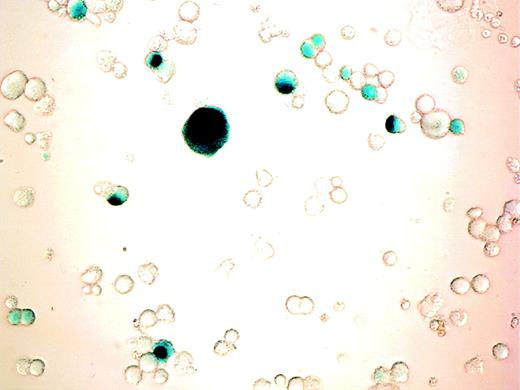

Cells were incubated with varying MOI of AdCMVhGFP, control virus, or vehicle on day 11 of culture and were harvested for cytometric analysis 24 to 72 hours later. MK expression of GFP was detected after 24 hours of viral incubation and increased over the next 48 hours (Fig 3). The efficiency of transduction increased with increasing MOI and incubation time (Table 2). There was a 10% reduction in cell viability for the highest MOI at 48 and 72 hours as determined by Trypan blue staining and scatter profile analyses. Incubation of cultured cells with AdCNLacZ also resulted in successful transduction with low cell toxicity (Fig4). Transduction efficiency at 4 days, as assessed by visualization of X-gal staining, was 9%, 18%, 22%, and 28% for MOI of 50, 100, 200, and 500, respectively.

β-gal expression in cultured cells after adenoviral transduction. CD34+ cells were cultured with PEG-rHuMGDF for 10 days before incubation with AdCNLacZ (MOI of 200). β-gal expression was visualized by light microscopy after cell fixation and X-gal staining as described in Materials and Methods. Photomicrograph of adenovirus infected cells (400×). Note the blue nuclear staining of successfully transduced cells. No blue coloration was detectable in any cell from samples that were similarly stained but were incubated with virus control.